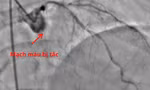

Chiếc răng bị gãy rơi vào đường thở của trẻ sau tai nạn được các bác sĩ lấy ra ngoài qua nội soi

BS Lý Phạm Hoàng Vinh, khoa Tai Mũi Họng, Bệnh viện Nhi Đồng 1, cho biết thăm khám lâm sàng kết hợp hình ảnh học ghi nhận bệnh nhi bị mất răng số 21. Từ chi tiết này, các bác sĩ nghĩ nhiều đến khả năng chiếc răng đã bị hít sặc vào đường thở trong lúc tai nạn nhưng không được phát hiện ngay. Kết quả kiểm tra tổng thể cho thấy, bệnh nhi bị vỡ xương sàn ổ mắt, đụng dập nhãn cầu, dị vật đường thở, chấn thương đầu và vết thương vùng đầu do tai nạn giao thông.

Trước nguy cơ biến chứng hô hấp nghiêm trọng, bệnh viện đã tổ chức hội chẩn liên chuyên khoa. Các bác sĩ quyết định nội soi đường thở khẩn, lấy thành công chiếc răng nằm trong khí quản của bệnh nhi. Theo BS Hoàng Vinh, các tai nạn gây chấn thương hàm mặt, răng gãy rất dễ bị hít vào đường thở mà triệu chứng ban đầu không rầm rộ nên dễ bỏ sót. Vì vậy, khi trẻ gặp tai nạn giao thông, dù còn tỉnh táo và triệu chứng nhẹ, vẫn cần được thăm khám đầy đủ tại cơ sở y tế có chuyên khoa.